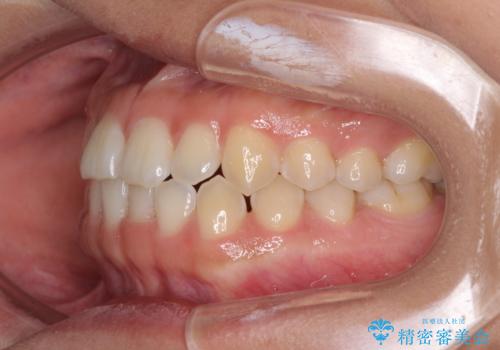

前歯の隙間を閉じたい 短期間でのワイヤー矯正

- 上の前歯の隙間を気にして来院された患者様です。

インビザラインの自己管理は自信がないとのことで、ワイヤー矯正により隙間を閉じていくこととしました。

下の前歯が上の前歯を突き上げるように咬合するため、咬み合わせの位置を改善しながら隙間を閉じていきました。

元々の歯並びが悪くなかったため、9ヶ月で綺麗に仕上がりました。